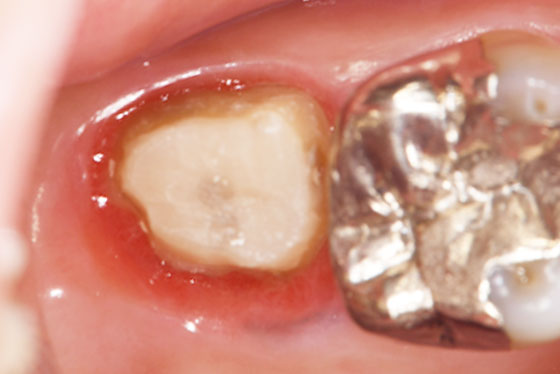

歯の上部が割れた場合と、歯の根が割れた場合とでは、治療法や治療の難易度が異なります。「歯の上部」が割れた場合は、基本的に抜歯せずに治療が可能です。しかし、「歯の根」が割れた場合、多くのケースは抜歯の選択となります。

しかし、「歯の根」が割れた場合でも、一度、その歯を意図的に抜歯し、割れた部分を処置して再度元に戻す「意図的再植術」を行うことで最終的には抜歯せずに治療ができることもあります。

以下、他院で「抜歯」と言われた歯を残したケースになります。

他院で「歯の根が割れてるので、抜歯になります」と言われた場合でも、実際は割れておらず、通常の根管治療で対応ができる場合があります。

そのため本来残せたはずの歯も抜歯になってしまうケースが意外に多くあります。

他院で抜歯と言われた場合でも、どうしても残したいとお考えの方、一度ご相談ください。当院では「セカンドオピニオン」も受け付けておりますので、お気軽にお問合せください。